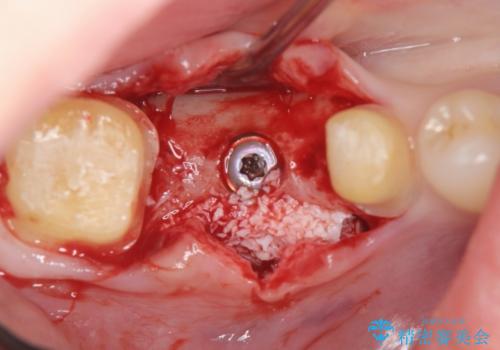

- 虫歯で歯を失い、インプラント治療を希望され来院されました。

吸収した骨を造骨にて補い、インプラントによる機能回復を計画します。

歯を失ってからの時間が経過し骨が吸収してしまっていても、造骨を行うことで予知性の高いインプラント治療を行うことができます。